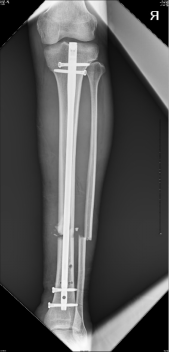

連接CO接骨機器人機械臂,調(diào)整操控桿機進行初步牽引復(fù)位。

初步復(fù)位完成后,CO接骨機器人牽引下置入髓內(nèi)釘